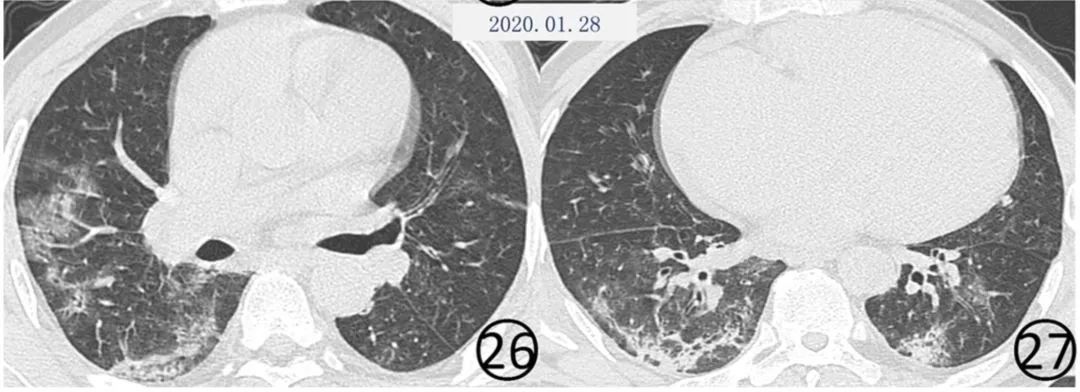

部分患者病变可以在较短的时间内演变为纤维化的索条影(图24,图25,图26,图27),这种纤维化表现是否为病变逆转的特点,仍有待于资料的进一步积累。

图24~27 男,60岁。首次(图24,25)CT平扫肺窗显示,两肺可见大片状磨玻璃阴影,右肺下叶前段有结节和晕征,新型冠状病毒核酸检测阴性。5 d后(图26,27)CT平扫肺窗显示,大片磨玻璃阴影有吸收,但是出现新发的斑片状磨玻璃阴影,其内有血管增粗,斜裂局限性增厚,两下肺有纤维化形成,其内可见扭曲的细支气管充气征